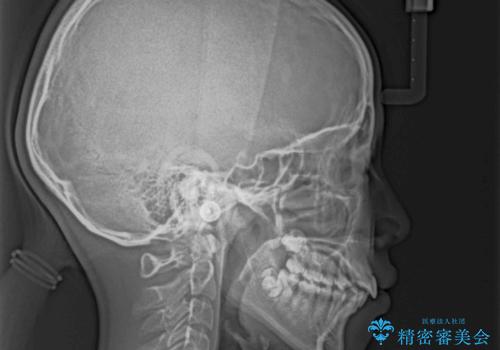

- 口元の突出感で口が閉じにくいとのことで来院された患者様です。

上下左右の第一小臼歯4本を抜歯し、ワイヤー装置での抜歯矯正を行うこととしました。

右側の咬み合わせは、上顎がやや前方位にある状態であったので、通常は補助装置を併用するのですが、高校生ということで補助装置なしで治療を行うこととしました。